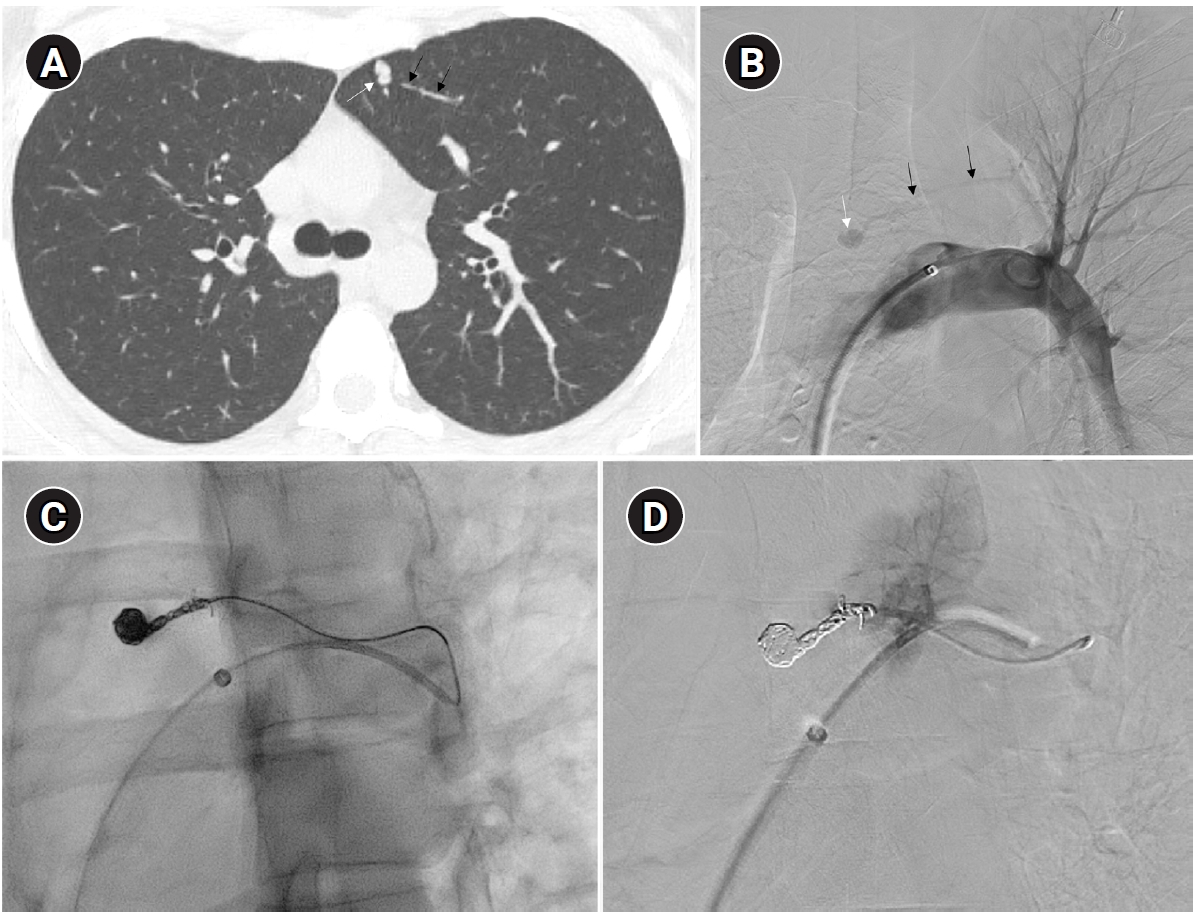

The images show a 38-year-old female patient undergoing pulmonary arteriovenous malformation embolization using an Amplatzer vascular plug. (A) A simple pulmonary arteriovenous malformation is observed in the right pulmonary angiography, and the feeding artery diameter is measured at 3.7 mm. (B) An 8-Fr, 80-cm guiding catheter and a 5-Fr Berenstein angled catheter were used to advance to the distal end of the feeding artery. (C) A 7-mm Amplatzer vascular plug type IV (arrow) was deployed at the distal portion of the feeding artery with a 100% oversizing. (D, E) The large venous sac (arrow) that was visible on the pre-procedure non-enhanced chest computed tomography (CT) (D) had only a trace remaining (arrow) on the CT performed 6 months later (E).

Fig. 4. The images show a 38-year-old female patient undergoing pulmonary arteriovenous malformation embolization using an Amplatzer vascular plug. (A) A simple pulmonary arteriovenous malformation is observed in the right pulmonary angiography, and the feeding artery diameter is measured at 3.7 mm. (B) An 8-Fr, 80-cm guiding catheter and a 5-Fr Berenstein angled catheter were used to advance to the distal end of the feeding artery. (C) A 7-mm Amplatzer vascular plug type IV (arrow) was deployed at the distal portion of the feeding artery with a 100% oversizing. (D, E) The large venous sac (arrow) that was visible on the pre-procedure non-enhanced chest computed tomography (CT) (D) had only a trace remaining (arrow) on the CT performed 6 months later (E).

Historically, detachable balloons were used as an embolization material; however, they are no longer utilized in current practice [18]. In the context of PAVM embolization, the use of coils, vascular plugs, or a combination of both is now standard practice [19-21]. Since the development of detachable coils, they have offered advantages over pushable coils, particularly in terms of repositioning during the procedure. They can even be fully retrieved and redeployed if necessary, enhancing procedural safety and control. It is crucial to prioritize minimizing the recanalization rate while ensuring the overall safety of the procedure when selecting the appropriate embolic materials and techniques. Feeding artery coil embolization was historically regarded as the standard approach, whereas venous sac embolization was discouraged because of the perceived risk of rupture [22]. However, with the introduction of newer venous sac embolization techniques, recent findings now indicate that tightly packing the venous sac with coils can achieve a higher success rate than the traditional feeding artery approach (Fig. 2) [22-25]. Additionally, vascular plugs, including micro-vascular plugs (Medtronic, Minneapolis, MN, USA) and Amplatzer vascular plugs (Abbott Vascular, Saint Paul, MN, USA) have also demonstrated a higher success rate compared to feeding artery coil embolization (Fig. 4) [26-28]. In the case of vascular plugs, the risk of device migration is relatively low. Moreover, an additional advantage is that the device can be repositioned if the sizing is not ideal or if it is not deployed in the exact desired location. This flexibility enhances the precision of the procedure (Fig. 5). In a recent European guideline, there is also a recommendation to consider vascular plug embolization as a first-line option whenever possible, rather than coil embolization [11]. Additionally, a recent meta-analysis recommended vascular plugs or venous sac coil embolization, noting that vascular plugs had a recanalization rate of 13.6% compared to 32.7% for coil-only embolization. Similarly, venous sac embolization showed a 3.8% recanalization rate, while feeding artery embolization had a rate of 24.3%. Additionally, a recent meta-analysis has recommended the use of vascular plug or venous sac coil embolization, as these techniques have demonstrated a lower persistence rate compared to other methods [21]. This shift is largely in response to the relatively high recanalization rate associated with feeding coil embolization. In the case of embolization using vascular plugs, the plug should be deployed at the most distal segment of the feeding artery just before the venous sac in order to preserve the normal pulmonary artery. Since the pulmonary artery contains less elastin and has a thinner wall compared to systemic arteries, it is more distensible [29]. Therefore, in the author's experience, oversizing by about 50% to 100% has been effective in reducing the recanalization rate. When performing venous sac coil embolization, it is important to use coils large enough to create a stable framing coil larger than the draining vein diameter, thereby preventing coil migration. After establishing this frame, the venous sac and the proximal feeding artery should be carefully packed to achieve complete occlusion.